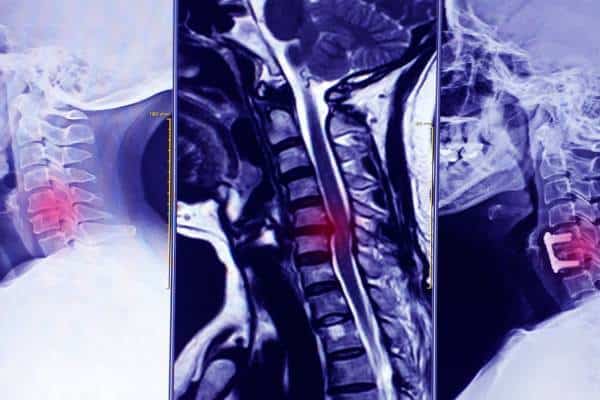

Cervical Decompression

Cervical decompression surgery is performed to relieve pressure on the spinal cord or nerve roots caused by narrowing of the spinal canal or foramina within the cervical spine. This may occur due to conditions such as disc herniation, spinal stenosis, or degenerative disc disease, leading to symptoms like neck pain, weakness, numbness, or reduced function.

Dr Fairhall provides detailed assessment and management of cervical spine conditions and performs cervical decompression surgery when clinically indicated. The goal is to relieve pressure on neural structures and improve both symptoms and spinal function.